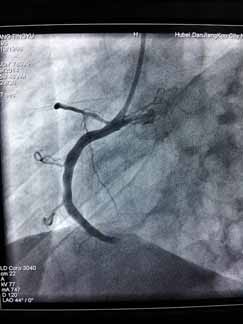

近日,烈日炎炎,急性心肌梗死高发,周六周日两天“120”急救车连续接诊两位急性心梗患者,到达我院后,心血管内科立即开通心梗绿色通道,最短时间内对两例病人实施急诊PCI,配合药物、抽吸导管及冠脉支架治疗,手术进行的非常顺利。门球时间均在60分钟内,堵塞血管立即开通,置入心脏支架,病人获得了最大收益,避免了急性心梗的高死亡率及不良后遗症。